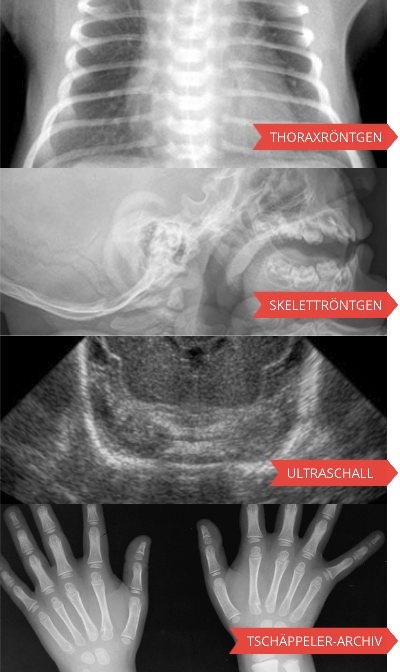

Pedirad